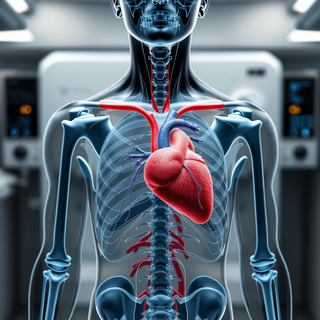

Simplify medical equipment specs for everyone.Open# Infusion Pump An infusion pump is a medical device used to deliver fluids, medications, or nutrients into a patient's body in controlled amounts. ## Purpose - Administer intravenous (IV) fluids, medications, blood products, and nutritional supplements - Provide precise control over delivery rates and volumes - Allow for continuous or intermittent administration ## Types 1. **Volumetric pumps**: Deliver larger volumes of fluids 2. **Syringe pumps**: For smaller volumes and more precise control 3. **Patient-controlled analgesia (PCA) pumps**: Allow patients to self-administer pain medication 4. **Ambulatory pumps**: Portable devices for mobile patients 5. **Enteral pumps**: For delivering nutrition directly to the gastrointestinal tract ## Key Features - Programmable delivery rates and volumes - Multiple delivery modes (continuous, intermittent, bolus) - Alarm systems for occlusions, air-in-line, low battery, etc. - Drug libraries with pre-programmed safety limits - Data logging and connectivity with electronic health records ## Safety Considerations - Proper programming to avoid over- or under-infusion - Regular maintenance and calibration - Battery backup systems - Infection control protocols for IV line management - Staff training on proper use and troubleshooting ## Common Procedures - IV fluid administration - Chemotherapy delivery - Antibiotic therapy - Pain management - Parenteral nutrition ## Usage Instructions 1. Verify patient identity and prescribed therapy 2. Prime tubing and connect to patient's IV access 3. Program pump with correct medication, dose, and rate 4. Start infusion and monitor regularly 5. Respond promptly to any alarms 6. Document administration in patient records

Simplify medical equipment specs for everyone.Open# Infusion Pump An infusion pump is a medical device used to deliver fluids, medications, or nutrients into a patient's body in controlled amounts. ## Purpose - Administer intravenous (IV) fluids, medications, blood products, and nutritional supplements - Provide precise control over delivery rates and volumes - Allow for continuous or intermittent administration ## Types 1. **Volumetric pumps**: Deliver larger volumes of fluids 2. **Syringe pumps**: For smaller volumes and more precise control 3. **Patient-controlled analgesia (PCA) pumps**: Allow patients to self-administer pain medication 4. **Ambulatory pumps**: Portable devices for mobile patients 5. **Enteral pumps**: For delivering nutrition directly to the gastrointestinal tract ## Key Features - Programmable delivery rates and volumes - Multiple delivery modes (continuous, intermittent, bolus) - Alarm systems for occlusions, air-in-line, low battery, etc. - Drug libraries with pre-programmed safety limits - Data logging and connectivity with electronic health records ## Safety Considerations - Proper programming to avoid over- or under-infusion - Regular maintenance and calibration - Battery backup systems - Infection control protocols for IV line management - Staff training on proper use and troubleshooting ## Common Procedures - IV fluid administration - Chemotherapy delivery - Antibiotic therapy - Pain management - Parenteral nutrition ## Usage Instructions 1. Verify patient identity and prescribed therapy 2. Prime tubing and connect to patient's IV access 3. Program pump with correct medication, dose, and rate 4. Start infusion and monitor regularly 5. Respond promptly to any alarms 6. Document administration in patient records -